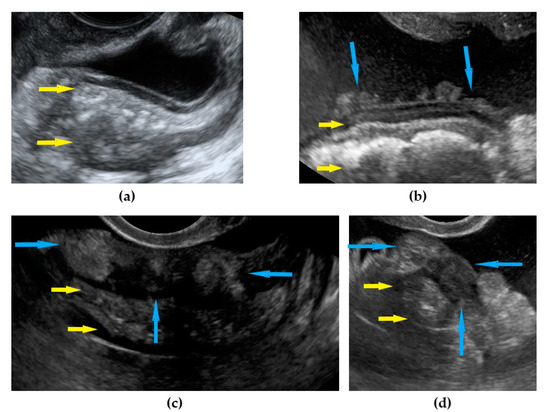

| Frozen pelvis | Massive pelvic involvement: hypoechogenic tissue in the peritoneum in the pouch of Douglas, forming cohesion between ovarian masses, bowel, uterus, and posterior pelvic wall. It manifests in the dynamic ultrasound examination: absence of sliding sign between the rectum and uterus/ovaries and between the uterus, urinary bladder, and pelvic walls. | Figure 12 | Video S12 |